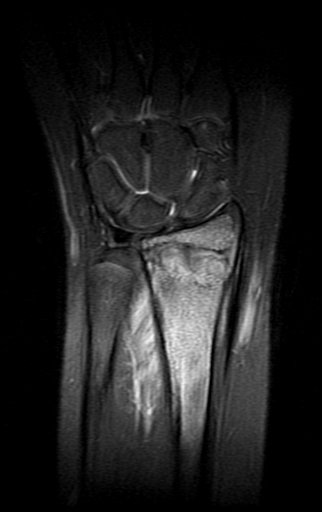

En la misma fecha, 23/05/2016, se le realizó un examen de resonancia magnética, como se muestra en las figuras 159 a 172.

Em 30 de maio de 2016, após seis meses de tratamento com Vimblastina EV, Mercaptopurina e Meticorten (50 mg) o paciente retorna para avaliação. Neste período teve um episódio de dor e edema do punho em Janeiro de 2016, cujas radiografias são apresentadas nas figuras 142 e 143. Manteve o punho imobilizado e reavaliou-se em 11-04-2016, figuras 144 e 145.